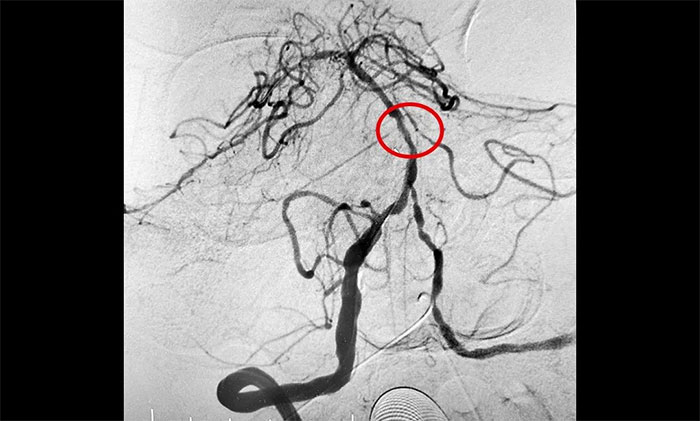

▲ 基底动脉顺利开通

11月20日,经过充分的准备工作,席刚明教授团队在介入团队协助下顺利实施了手术。术中凶险的就是反复球囊扩张狭窄,如果掌握不好扩张球囊的位置和扩张速度,势必造成更复杂的血管夹层甚至出血。历时3个多小时奋战,席刚明教授凭借丰富的临床经验及精准的手法顺利地于基底动脉狭窄处进行球囊扩张,患者基底动脉得以完全开通,手术获得圆满成功,打开了患者的“生命通道”。

术后,患者顺利苏醒,无新发功能缺损,肢体无力、肢体麻木症状得到改善。